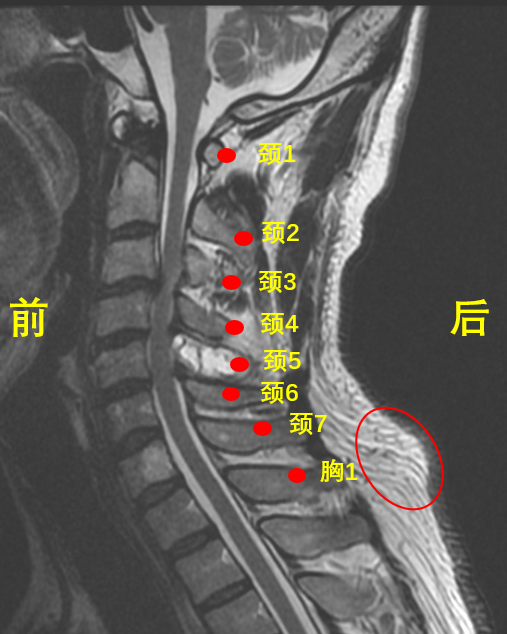

它是颈胸交界(第7颈椎 + 第1胸椎) 异常凸起的包块,是颈椎发出的健康警报,年轻人越来越多,再不管会越来越难受、越来越丑!

医学上没有 “富贵包” 这个正式病名,它多是上交叉综合征的典型表现,也叫颈背部脂肪垫、颈椎后凸畸形。

颈椎曲度变直 / 反弓,诱发颈椎病、间盘突出